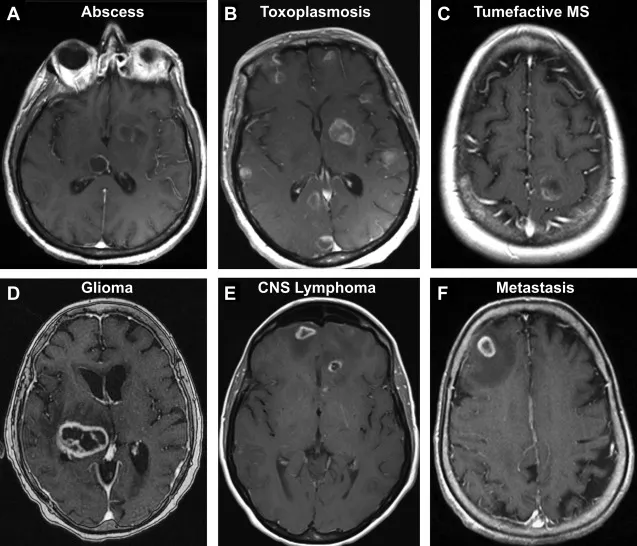

⭐ Ring-enhancing lesions on MRI are classic. 📌 Mnemonic: MAGIC DR L (Metastasis, Abscess, Glioblastoma, Infarct, Contusion, Demyelinating disease, Radiation necrosis, Lymphoma).